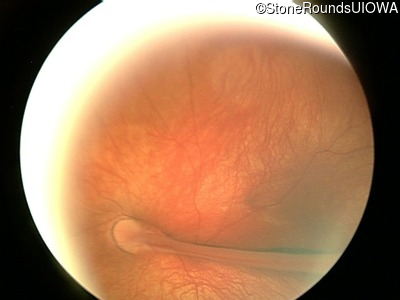

Visit at age: 16 years

Fundus Photography - Right - 20/300

Exemplar